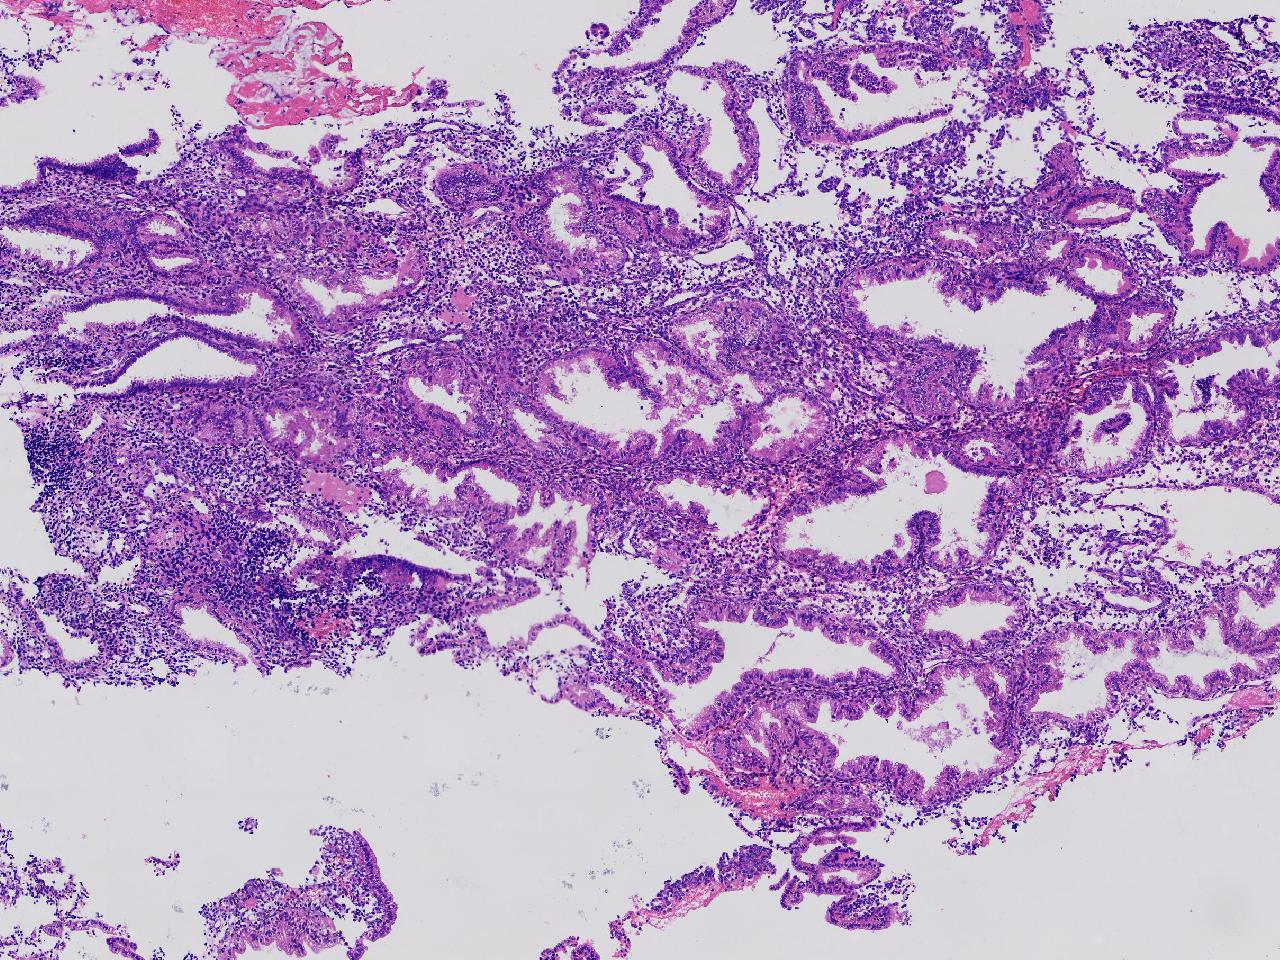

性别

女

年龄

45岁

临床诊断

阴道不规则出血20余天,

一般病史

彩超示:宫腔内见约41X11毫米的不均质回声区。宫腔镜示:宫腔形态正常,内膜粉红,不规则增厚。

标本名称

子宫内膜

大体所见

灰粉色不整形软组织多块,1.5X1X0.6厘米。

分泌反应子宫内膜,伴有出血。

晚泌期及月经早期改变,局部呈啫酸性乳头状化生改变。